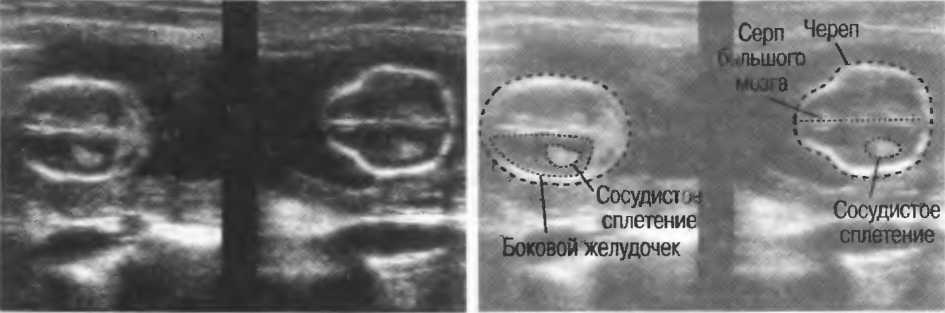

Рис.8б. Два аксиальных среза головки плода, развернутые на 180°. Перед проведением исследования ориентация изображения на экране должна быть проверена, как показано на рис. 8а.